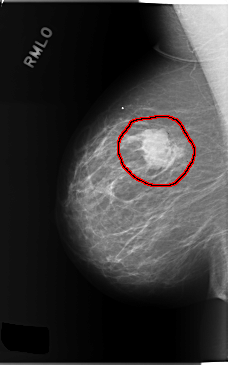

FILE: C_0147_1.RIGHT_MLO.OVERLAY

TOTAL_ABNORMALITIES 1

ABNORMALITY 1

LESION_TYPE MASS SHAPE LOBULATED MARGINS MICROLOBULATED

ASSESSMENT 5

SUBTLETY 5

PATHOLOGY MALIGNANT

TOTAL_OUTLINES 1

BOUNDARY